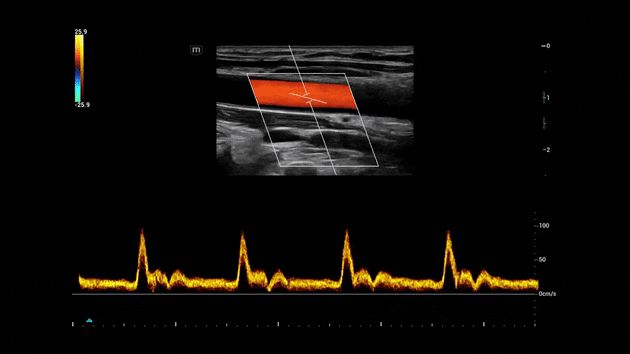

Regolazione automatica dell'angolo e della posizione della ROI

La funzionalità distintiva di Mindray che consente di ridurre i passaggi di scansione ripetitivi e dispendiosi in termini di tempo durante gli esami vascolari. Smart Track offre il rilevamento intelligente e in tempo reale dei vasi e l'ottimizzazione dell'immagine in tempo reale di Colore e PW.

Consona Series Cardiovascular Solution - Smart Track feature clinical image